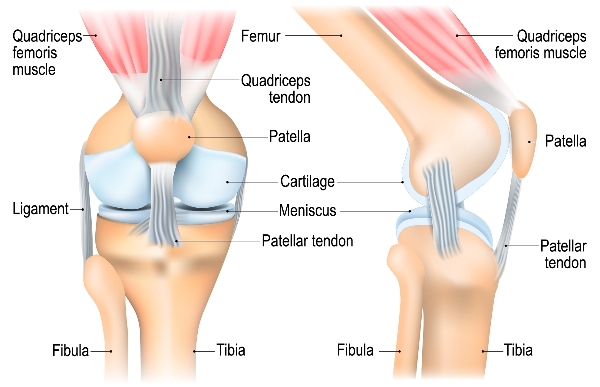

The knee is the largest joint in the body. It comprises of the lower part of the thighbone (femur) and upper part of the shinbone (tibia) as well as the kneecap (patella).

Covering all three bones is a smooth coating called cartilage which protects the bones and enables them to move easily.